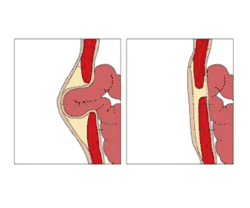

An umbilical hernia is a health condition where the abdominal wall behind the navel is damaged. It may cause the navel to bulge outwards—the bulge consisting of abdominal fat from the greater omentum or occasionally parts of the small intestine. The bulge can often be pressed back through the hole in the abdominal wall, and may "pop out" when coughing or otherwise acting to increase intra-abdominal pressure. Treatment is surgical, and surgery may be performed for cosmetic as well as health-related reasons.

Importantly, an umbilical hernia must be distinguished from a paraumbilical hernia, which occurs in adults and involves a defect in the midline near to the umbilicus, and from omphalocele.

An umbilical hernia can be fixed in two different ways. The surgeon can opt to stitch the walls of the abdomen or place mesh over the opening and stitch it to the abdominal walls. The latter is of a stronger hold and is commonly used for larger defects in the abdominal wall. Most surgeons will not repair the hernia until 5–6 years after the baby is born. Most umbilical hernias in infants and children close spontaneously and rarely have complications of gastrointestinal-content incarcerations.[10]

If hernias are symptomatic and disturb daily activity or have had episodes of threatening incarceration, preventive surgical treatment can be considered. The surgery is performed under anaesthesia, while the surgeon identifies the edges of the defect and bring them together permanently using either suture or mesh.[14] Small umbilical hernias are often successfully repaired with suture, while larger hernias may require a suitable mesh,[15] although some surgeons advocate mesh treatment for most hernias. The most common complications for both techniques are superficial wound infections and recurrence of the hernia[16] and some people experience pain at the surgical site.[17]